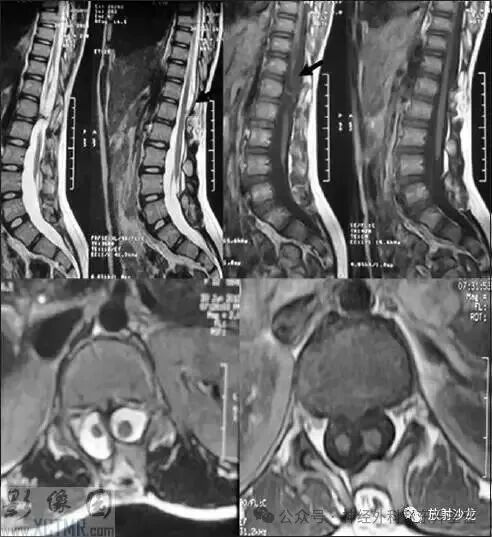

脊髓纵裂是怎么回事?脊髓分叉怎么办?

简单来说,脊髓纵裂是一种先天性的脊柱脊髓发育畸形,指的是脊髓被一个骨性、软骨性或纤维性的“间隔”在中间分开,变成了左右两半。

1. 它不是完全断裂: “纵裂”是纵向的分开,脊髓的两半通常仍然在间隔的上方和下方重新合并为一条完整的脊髓。真正可怕的是这个“间隔”对脊髓的固定、牵拉和压迫。

· Ⅰ型: 两个半侧脊髓有自己独立的硬脊膜鞘,中间通常是一个骨性或软骨性间隔。这个类型更需要手术干预。

· Ⅱ型: 两个半侧脊髓共享一个硬脊膜鞘,中间是一个纤维性间隔。